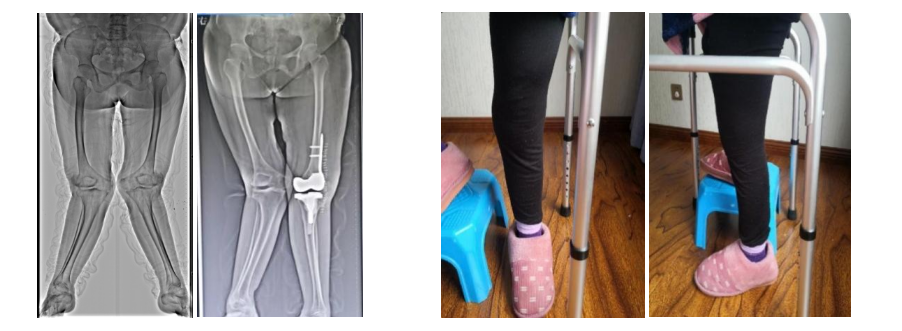

第二次术后复查X片影像 第二次术前及术后照片

术后3月患者左膝关节屈伸功能正常,膝关节疼痛消失,左腿已经完全看不出之前做过手术,患者及家属对此次手术效果十分满意。术后7月,患者虽然已能靠左腿行走,但患者右膝关节疼痛仍然严重,患者再次来我科找到左主任,要求做右膝关节手术。

2022年9月29日,经过周密的术前准备及规划,再次为患者在持续硬膜外麻醉下行右膝关节松解、髌骨成形、LCCK全膝关节置换术,手术顺利。术后,患者在我院康复科进行功能训练,恢复情况良好。